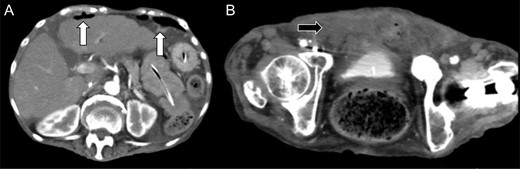

She was given an antibiotic (meropenem 0.5 g, every 8 h), but the next day, the abdominal pain worsened. Laboratory test showed elevation of the inflammation reaction values, and enhanced CT showed free air in the abdominal cavity (Fig. 2A), with increased fluid collection in the anterior space of the bladder (Fig. 2B). We performed emergency laparotomy for suspicion of digestive tract perforation. There was a small hole at the dome of the urinary bladder and another at the peritoneum, and very thick pus extruded into the abdominal cavity. We opened the front part of the urinary bladder, sutured the hole and sutured the bladder to close it. A permanent urinary catheter was placed for bladder drainage and decompression. The postoperative course was uneventful, and the inflammation reaction improved. She was discharged on the 21st postoperative day and had no recurrence since then.

Enhanced abdominal computed tomography 1 day after admission showing (A) free air in the abdominal cavity (white arrow) and (B) massive fluid collection in the posterior space of the urinary bladder (black arrow).